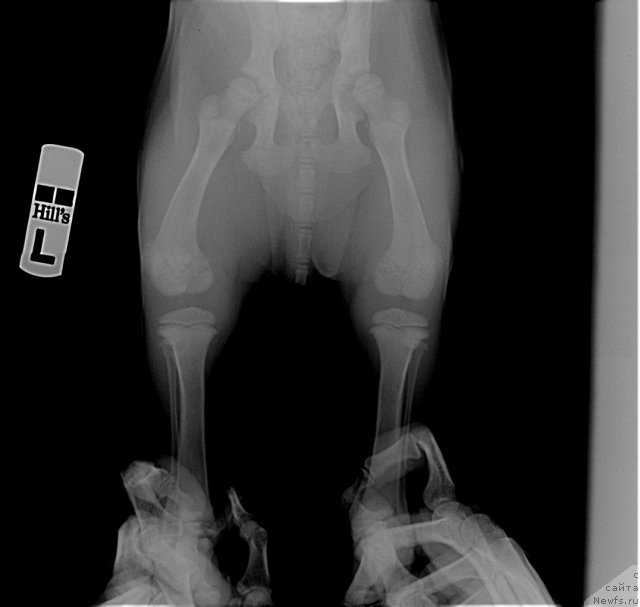

Посмотрите на суставы 2-х месячного щенка лабрадора. Насколько большие ростовые зоны. Какие огромные расстояния между костями суставов. И насколько еще не сформированны суставы. Особенно локтевые. А это собака гораздо легче ньюфаундленда. На него просто наступила сука. И такие травмы.

Фотография № 116289

Фотография № 116290

Фотография № 116291